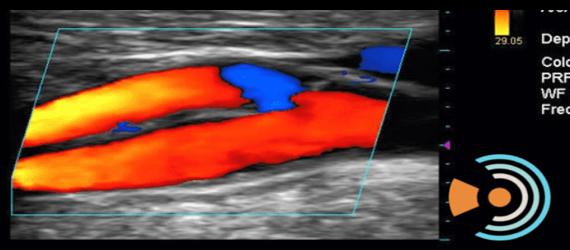

Doppler Color

En este tipo de Doppler, se utiliza una computadora que se encarga en convertir las ondas sonoras en diferentes colores que muestran con presición la velocidad y la dirección de la sangre en tiempo real.